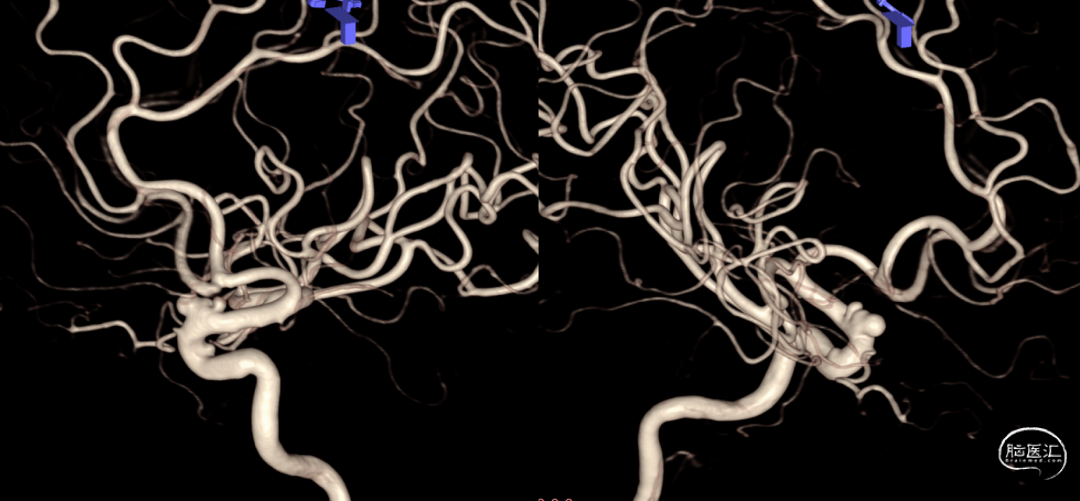

术前造影:

右颈

左椎